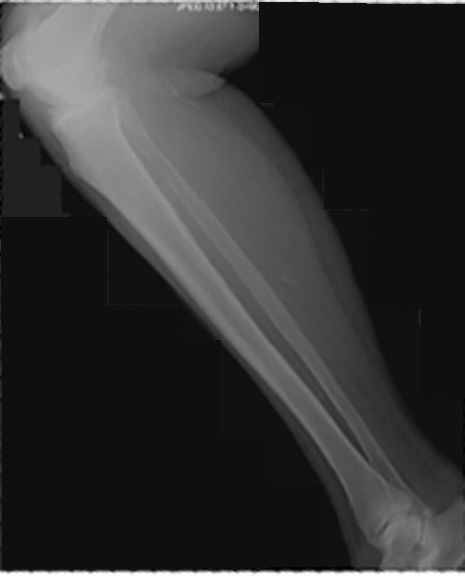

Identify the parts seen. Click the image for labeling.